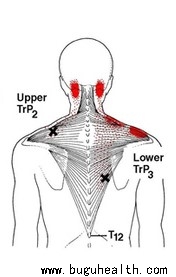

- 布骨医学科普:颈肩不适、上交叉、翼状肩,都与这块肌肉有关,却总被忽略! 布骨康复医疗中心 ,2021-06-11

- 很多男性都渴望拥有强壮健美的背阔肌,但其实这块肌肉才是新一代男人性感的代名词。在我们都熟悉的「上交叉综合征」处理中,胸肌、斜方肌紧张人尽皆知,这块肌肉却总被忽略。对于气短、肋痛、翼状肩胛等常见症状,这块肌肉才是其中元凶。今天我们就来为大家分享这块默默无闻,其实十分重要的肌肉――「前锯肌」。.....